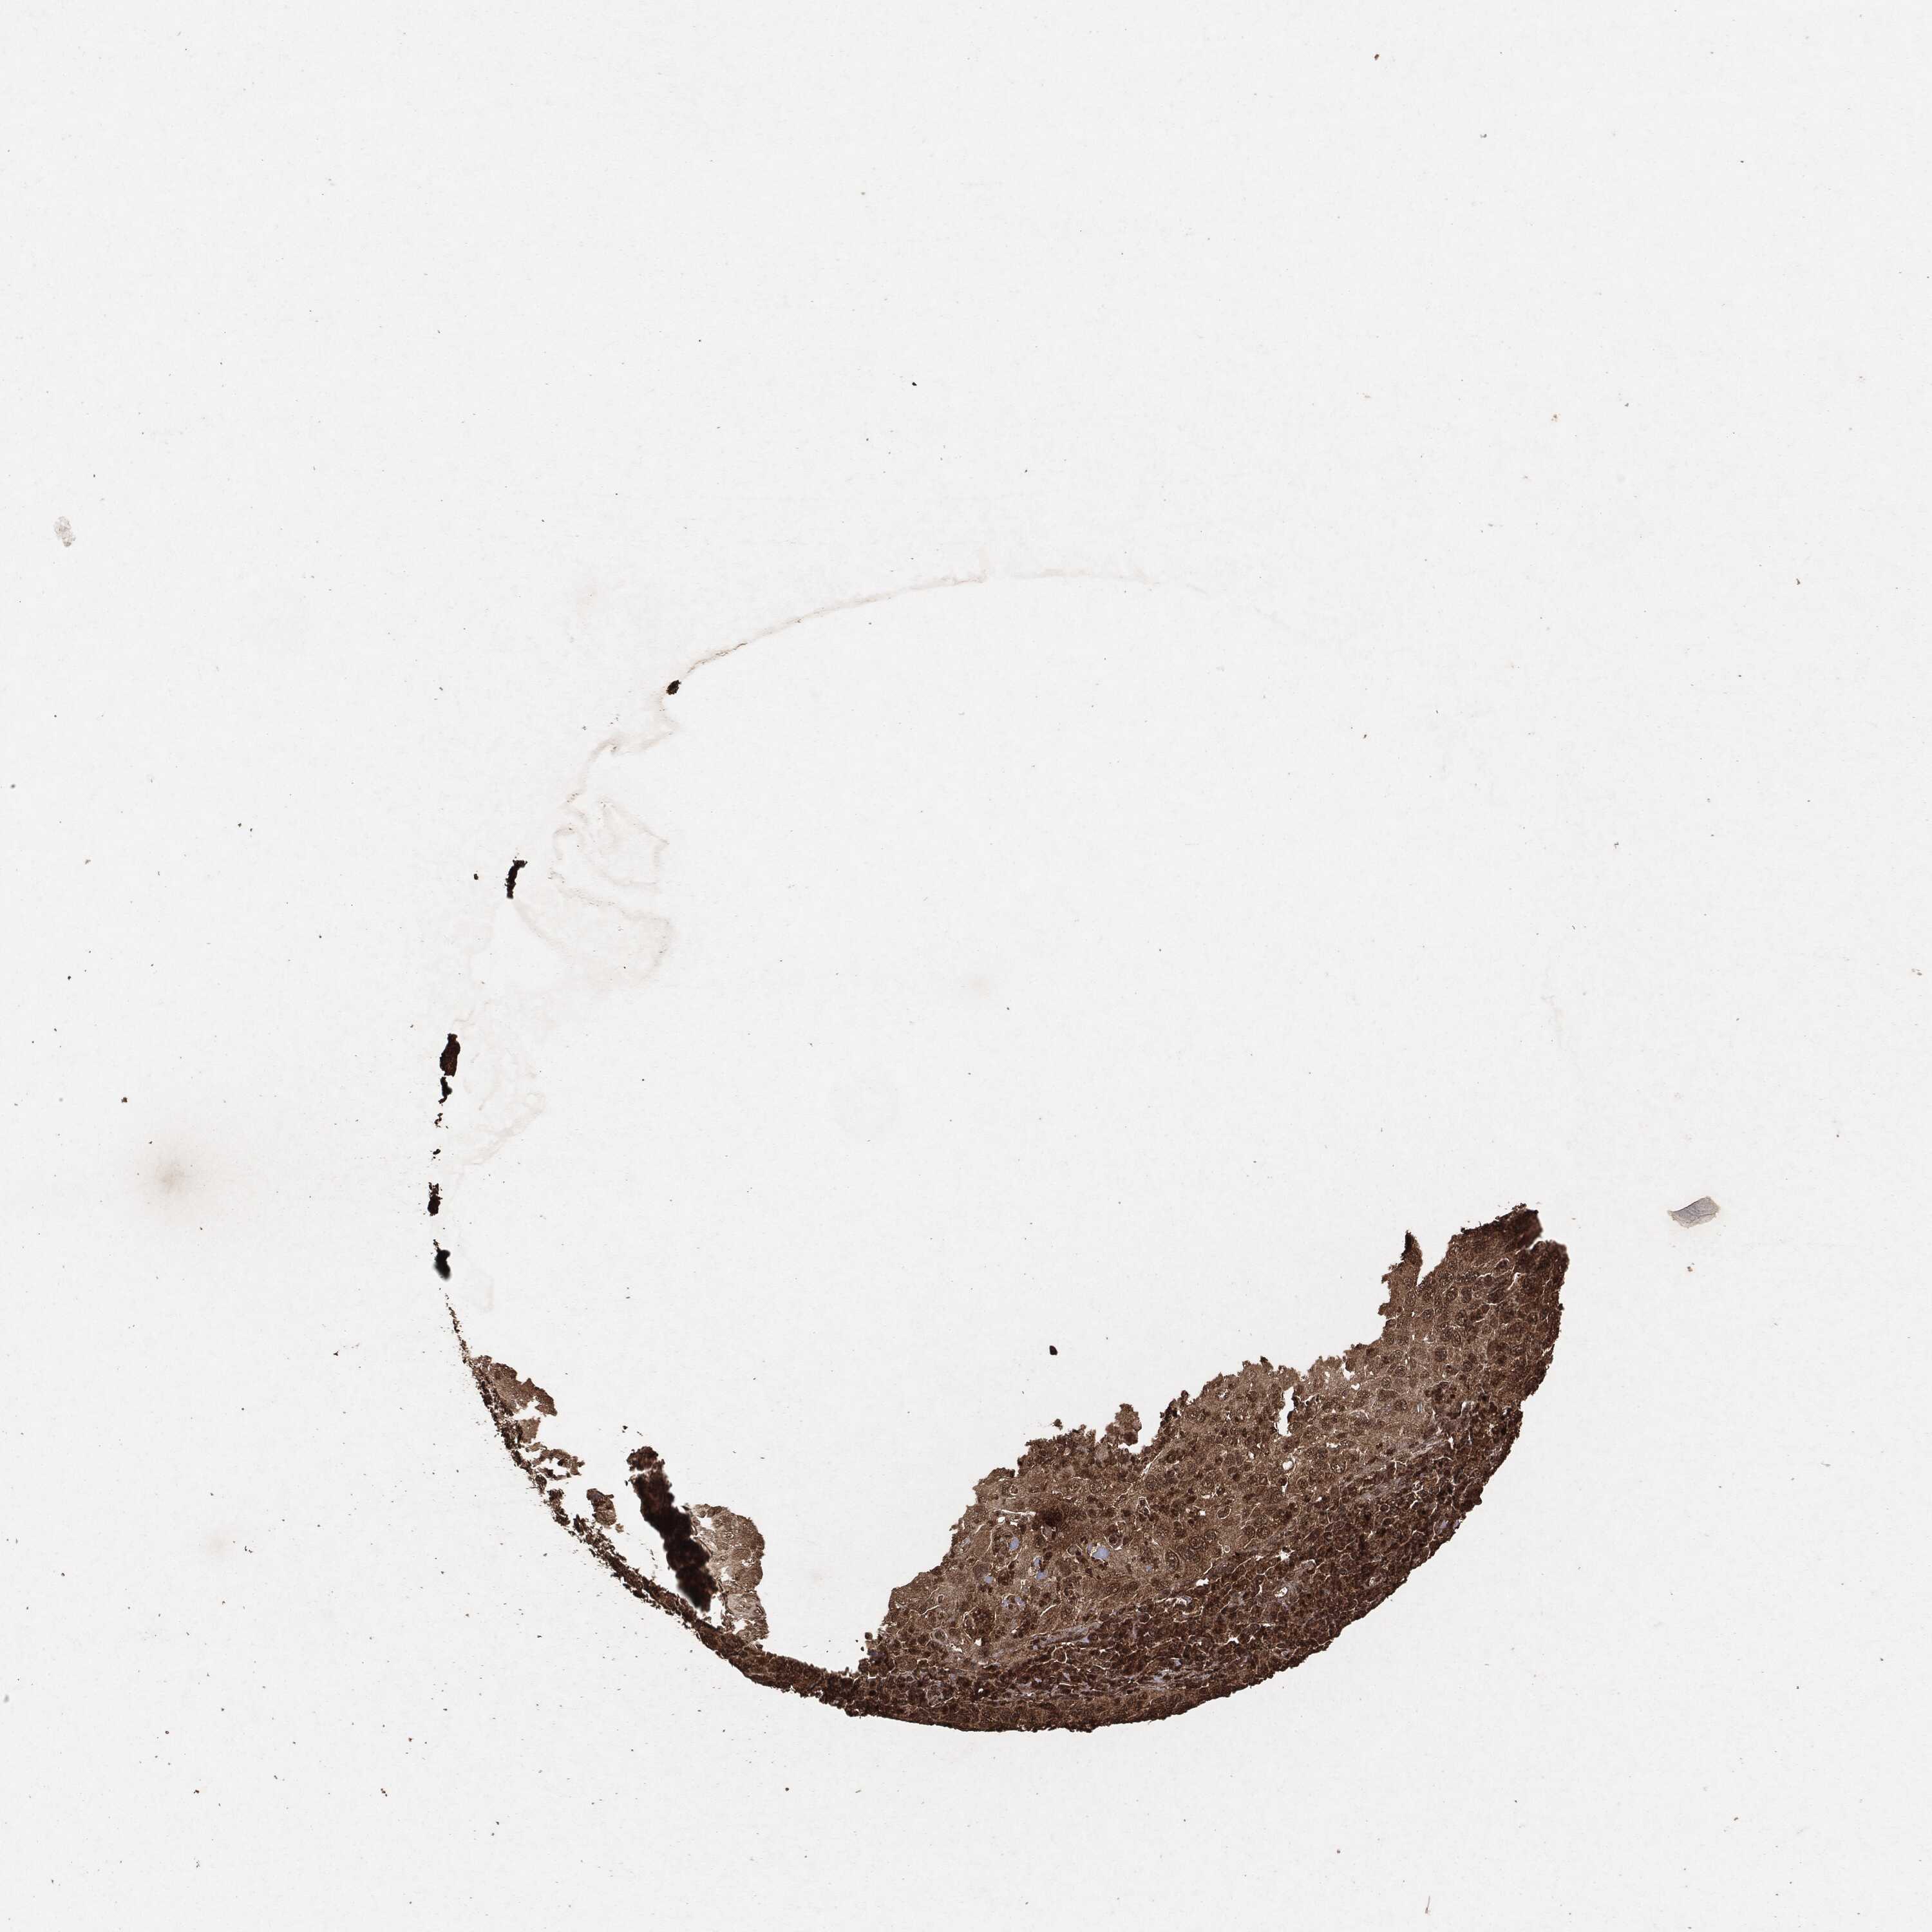

CERVICAL CANCER - Protein expressioni

A mouse-over function shows sample information and annotation data. Click on an image to view it in a full screen mode. Samples can be filtered based on level of antibody staining by selecting one or several of the following categories: high, medium, low and not detected. The assay and annotation is described here.

Note that samples used for immunohistochemistry by the Human Protein Atlas do not correspond to samples in the TCGA dataset.

Antibody stainingi

Antibody staining in the annotated cell types in the current human tissue is reported as not detected, low, medium, or high, based on conventional immunohistochemistry profiling in selected tissues. This score is based on the combination of the staining intensity and fraction of stained cells.

Each image is clickable and will lead to virtual microscopy that enables deeper exploration of all samples and also displays staining intensity scores, fraction scores and subcellular localization as well as patient and tissue information for each sample.